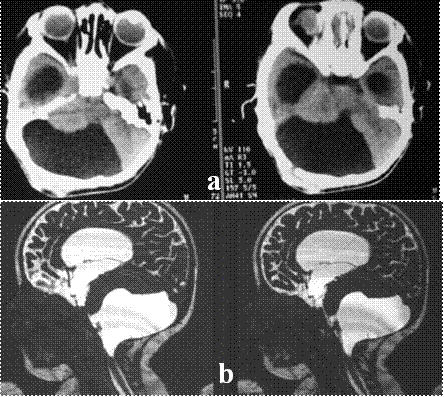

Resim 6: (a) ve

(b) yatay ve dikey düzlemlerdeki MRG görüntülerinde üçüncü karıncığı dolduran ve yan karıncıkların genişlemesine neden olan suprasellar araknoid kistin ameliyat öncesi görüntüleri,

(c) ve

(d) endoskopik ameliyat sonrası kistin küçüldüğü ve yan karıncıklardaki genişlemenin azaldığı izlenmektedir.